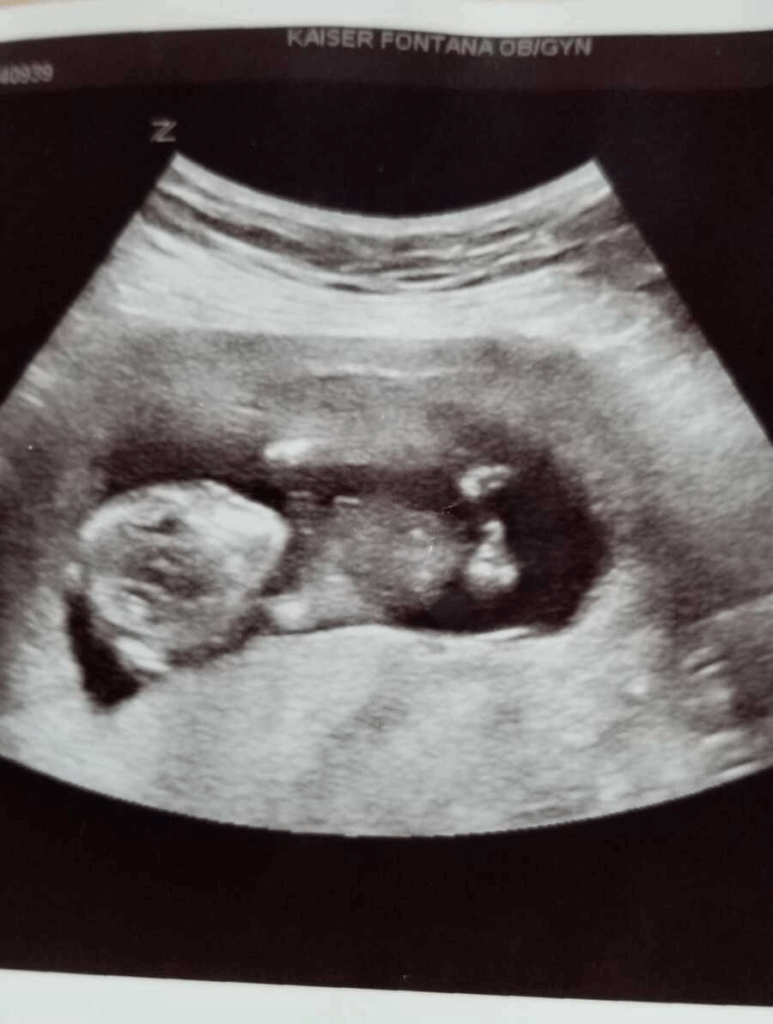

Around 30 weeks, I had a vivid dream that I gave birth to a baby boy with lots of hair who was sick in the NICU. The dream left me uneasy, but I tried not to worry. The rest of the pregnancy was normal, and everything looked perfect.